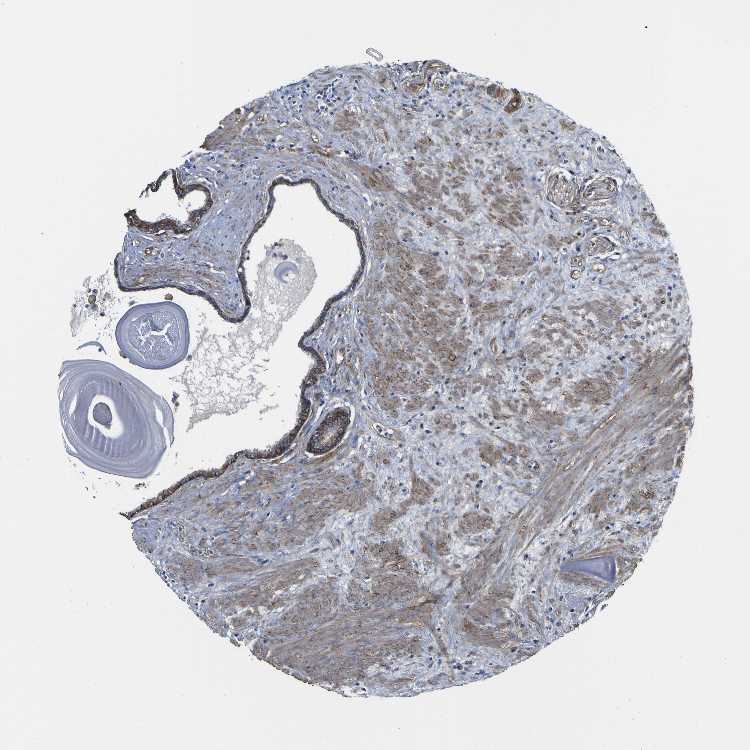

TISSUE PRIMARY DATA SEMINAL VESICLE Show tissue menu

SEMINAL VESICLE - Antibody stainingi

Antibody staining in the annotated cell types in the current human tissue is reported as not detected, low, medium, or high, based on conventional immunohistochemistry profiling in selected tissues. This score is based on the combination of the staining intensity and fraction of stained cells.

Each image is clickable and will lead to virtual microscopy that enables deeper exploration of all samples and also displays staining intensity scores, fraction scores and subcellular localization as well as patient and tissue information for each sample.

Antibody HPA011906Antibody CAB002428

Glandular cells MediumHigh